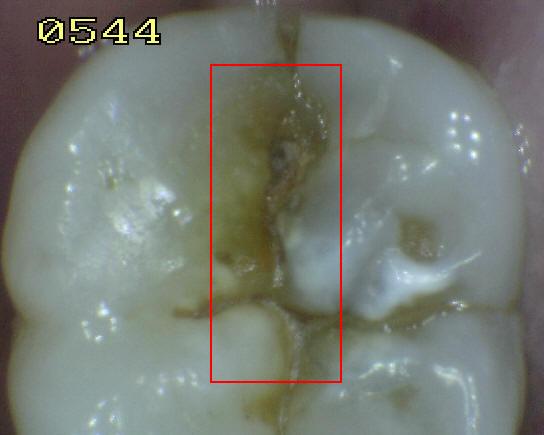

Código 5:

Cavidad detectable con dentina visible hasta la

mitad de la superficie

- Hay una cavidad en el esmalte opaco

o decolorado, dejando al descubierto la dentina. El diente

visto en estado húmedo puede haber oscurecimiento de la

dentina visible a través del esmalte. Una vez seco, hay

evidencia visual de la pérdida de la estructura del diente a la

entrada o dentro de la fosa o fisura, cavitación franca

> 0,5 mm hasta la mitad de la superficie dental. Hay evidencia visual de

desmineralización ( blanco opaco, de color marrón o paredes negras

ó de color marrón) en la entrada o dentro de la fosa o fisura. A juicio

del examinador se observa dentina expuesta en el piso y paredes de la

cavidad.

- La sonda de la OMS / IPC / PSR

se puede utilizar suavemente para confirmar la presencia de una

cavidad, al parecer en la dentina. Esto se consigue deslizando el extremo de la bola a lo

largo de la fosa o fisura sospechoso y una cavidad de la dentina se

detecta si el balón entra en la abertura de la cavidad y en la opinión

del examinador en la base de la cavidad se encuentra la dentina.